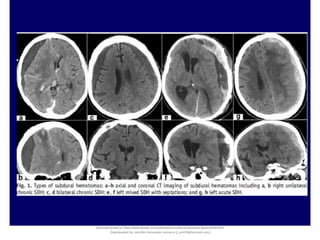

Acute SDH is readily visualized on head CT as a high-density crescentic collection across the

hemispheric convexity